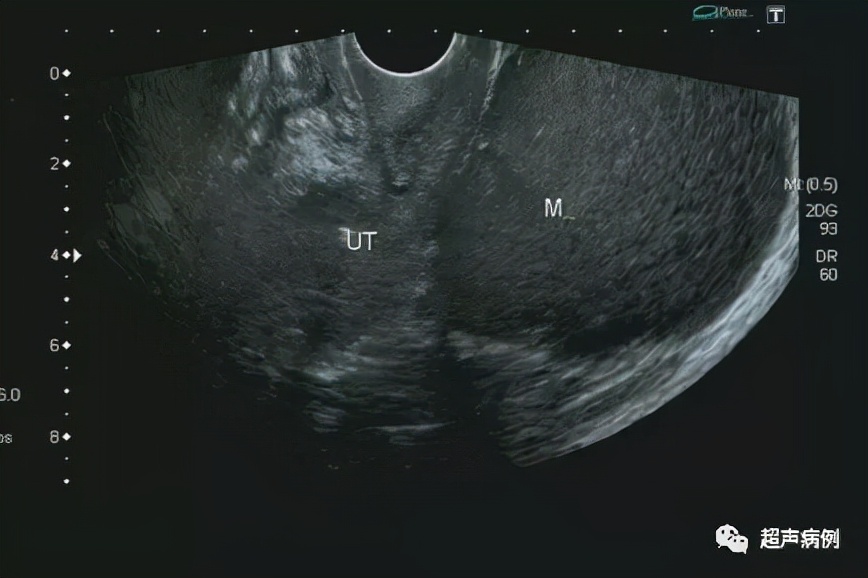

张珊(化名),女,62岁,因“左侧臀部疼痛1天,发现盆腔包块半天”入院。

超声检查:

前位子宫,形态、大小正常

在子宫后方盆腔内查见一约10.4x9.7x7.3cm无回声区

形态规则,边界清楚,内透声差,呈毛玻璃样改变

内可见强回声分隔

CDFI:该无回声区内部及周边未见明显血流信号。

双侧卵巢显示不清。